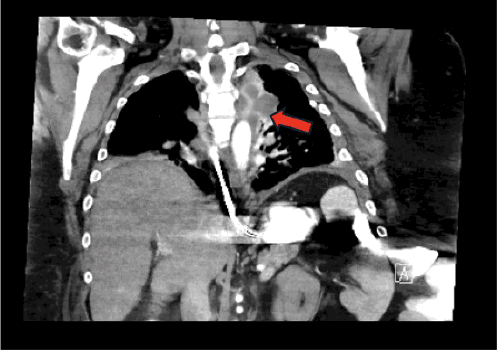

A 51-year-old morbidly obese male (body mass index [BMI] 47 kg/m²) with a remote history of laparoscopic cholecystectomy presented to the emergency department complaining of left-sided abdominal pain, nausea, and vomiting. An initial abdominal computed tomography (CT) scan revealed a large, left-sided lateral ventral hernia containing incarcerated bowel loops, consistent with a partial small bowel obstruction. Notably, due to the patient’s body habitus, the entirety of the hernia sac was not completely visualized on this initial study (Figure 1).

Figure 1. Initial CT Demonstrating Large Left Flank Hernia with Incomplete Visualization. Published with Permission

Axial view from the initial abdominal CT scan on presentation. The images demonstrate a large, left-sided lateral ventral hernia containing bowel loops. Note the incomplete visualization of the entire hernia sac due to the patient’s body habitus, with possible early fluid accumulation noted near the subcostal margin (arrow)

Coronal view from the initial abdominal CT scan on presentation. The images demonstrate a large, left-sided lateral ventral hernia containing bowel loops. Note the incomplete visualization of the entire hernia sac due to the patient’s body habitus, with possible early fluid accumulation noted near the subcostal margin

The patient was initially managed conservatively with bowel rest, intravenous hydration, and electrolyte repletion, targeting standard resuscitation parameters (mean arterial pressure >65 mmHg, heart rate <120 bpm, urine output ≥0.5 mL/kg/hr, capillary refill <2 seconds, and normalization of BUN, creatinine, electrolytes, and lactate). A nasogastric tube was placed for decompression, and intravenous analgesia was administered judiciously, avoiding narcotics where possible. Serial laboratory evaluations and physical examinations were performed to monitor for signs of worsening systemic inflammatory response, metabolic acidosis, increasing abdominal distension, or the development of peritonitis. Despite these measures, on hospital day five, the patient experienced a significant clinical deterioration, manifesting as sepsis and acute respiratory failure. A repeat CT scan at this time demonstrated a new, large, loculated, mixed-density pleural effusion on the left side (Figure 2). Crucially, this scan provided complete visualization of the hernia sac, revealing a persistent small bowel obstruction and a new extraperitoneal fluid collection within the abdominal wall, which appeared to be tracking superiorly into the pleural cavity (Figure 3).